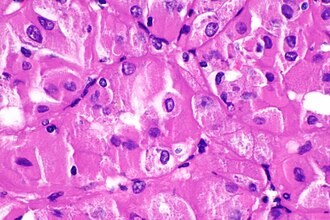

A renal tumour with an eosinophilic cytoplasm (chromophobe RCC). (WC/Nephron)

Renal tumours with eosinophilic cytoplasm, also eosinophilic renal tumours and kidney tumours with eosinophilic cytoplasm, are relatively common and have a differential diagnosis.